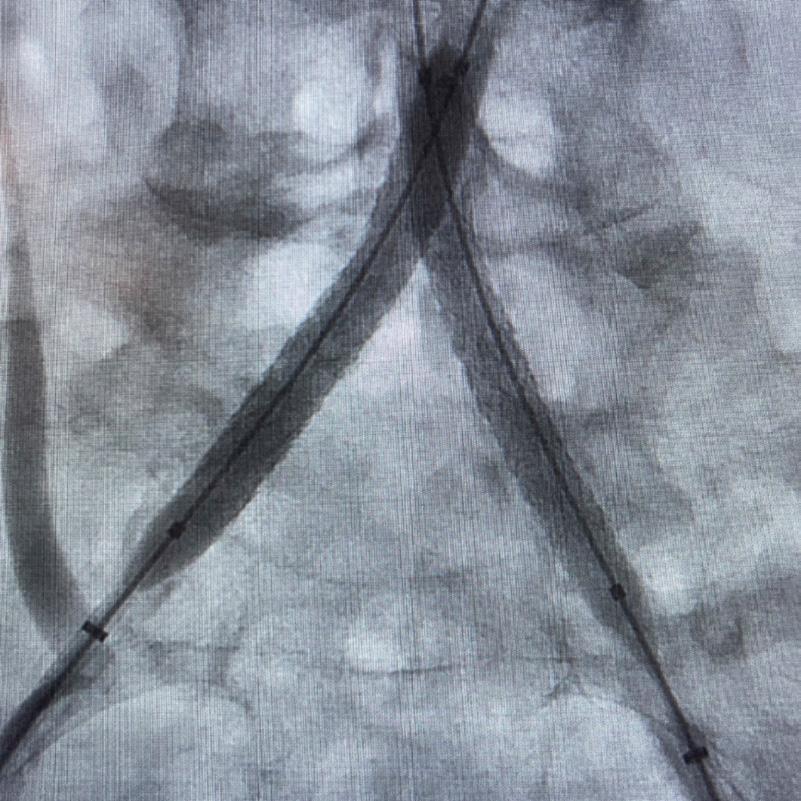

healthy reference vessel diameter (RVD) was 9.5mm. He would require a fenestrated repair of the AAA along with complex iliac stenosis treatment, and extensive bilateral common femoral endarterectomies.

Further, we were concerned we would not be able to advance the 19F fenestrated graft. The endograft was prepared, and then both femoral arteries were exposed. We attempted delivery of the endograft via the right common iliac access. This failed. We then attempted delivery on the contralateral side. Despite multiple attempts, we made little progress. A 10x30mm Shockwave L 6 catheter was selected, and a total of 150 pulses were delivered to each iliac artery at just 4atm. This not only allowed for the delivery of our FEVAR graft but also the full unrestricted expansion of the endograft limbs in the common iliac arteries.

Figure 4. Graft delivery